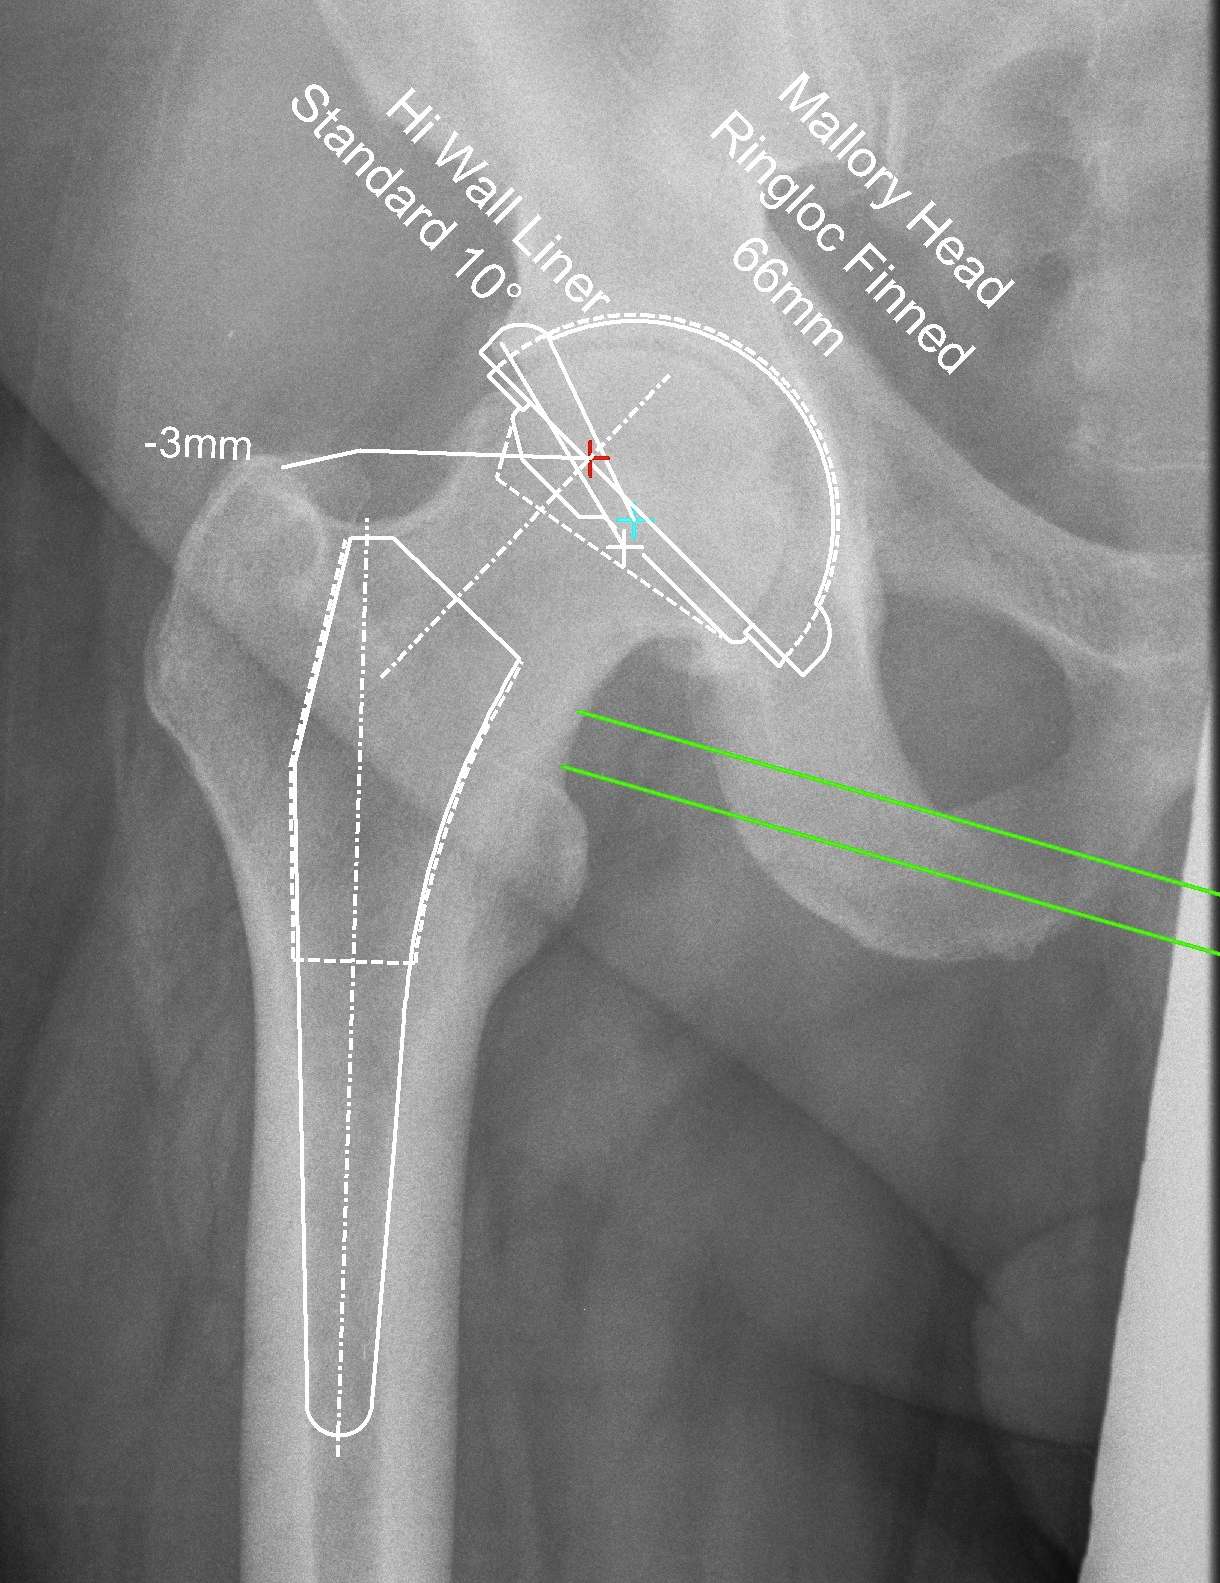

Reproduce the normal anatomical centre of rotation

Restore femoral offset

Maintain equal leg lengths

Usually template off normal hip

1. LLD

2. Offset

3. Femoral component

4. Acetabular component

5. Osteotomy / femoral seating